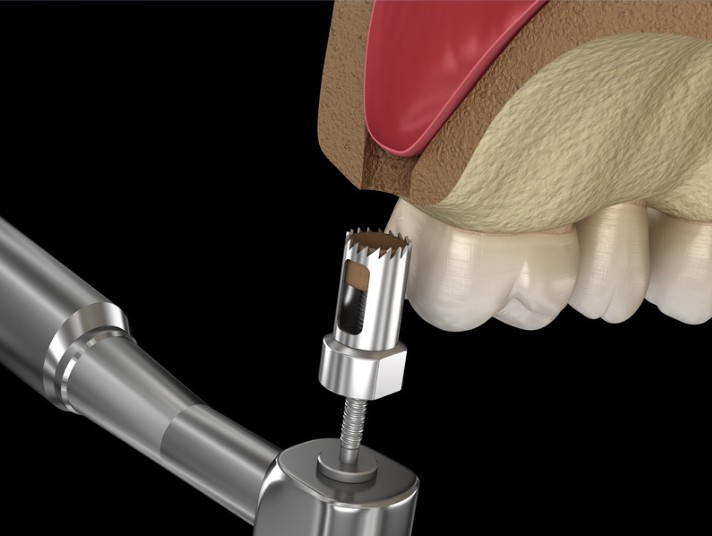

Implantes dentales

Si perdiste una o varias piezas dentales, los implantes son una excelente solución. Son estructuras de titanio que se integran al hueso y funcionan como raíces artificiales. Lo mejor: no se nota la diferencia con un diente natural. Yo misma realizo la cirugía y la planeación, todo en el mismo lugar.

Cirugía de implantes dentales

A diferencia de muchos lugares donde solo hacen la parte estética, yo realizo la cirugía completa de colocación de implantes. Esto permite tener un control total del proceso, desde la evaluación hasta el resultado final. Todo en manos de una cirujana maxilofacial.

Elevación del seno maxilar

Cuando no hay suficiente hueso en la parte posterior del maxilar superior, este procedimiento permite aumentar la altura del hueso para luego colocar implantes dentales. Es una cirugía delicada, pero muy segura cuando la hace un especialista.

Cirugía regenerativa de injertos óseos

En casos donde el hueso se ha perdido, ya sea por infecciones o por falta de dientes, podemos regenerarlo mediante injertos. Esto es clave para colocar implantes o recuperar la estructura facial. Utilizamos materiales de alta calidad y técnicas avanzadas.